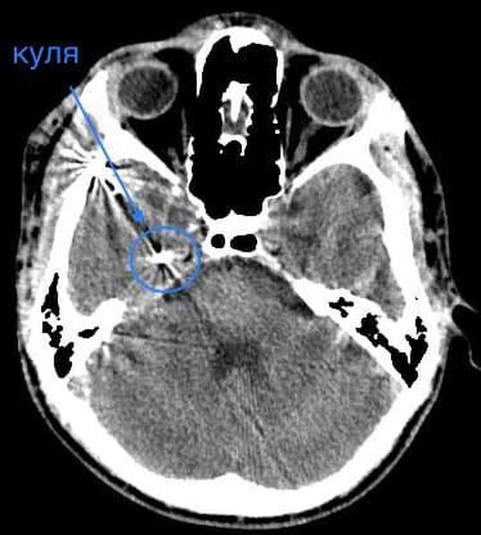

Куля зупинилась у сантиметрі від надзвичайно важливої судини

«Тиждень тому ввечері, саме перед важливою поїздкою до столиці, до нас поступив молодий хлопчина 16 років із травмою головного мозку. І травма ця дуже незвичайна – результат необережного поводження з пневматичною зброєю. Здавалось би – досить проста зброя, досить доросла дитина. І от результат необдуманого вчинку – потрапляння кулі в головний мозок із руйнацією скроневої кістки та частини головного мозку», – йдеться у дописі.

За словами нейрохірурга, підлітку провели невідкладну операцію та вилучили стороннє тіло, видалили пошкоджені тканини і відновили цілісність збережених тканин. На щастя, куля зупинилась у сантиметрі від надзвичайно важливої судини і права скронева частка (яка пошкодилась в результаті травми) – функціонально незначима.